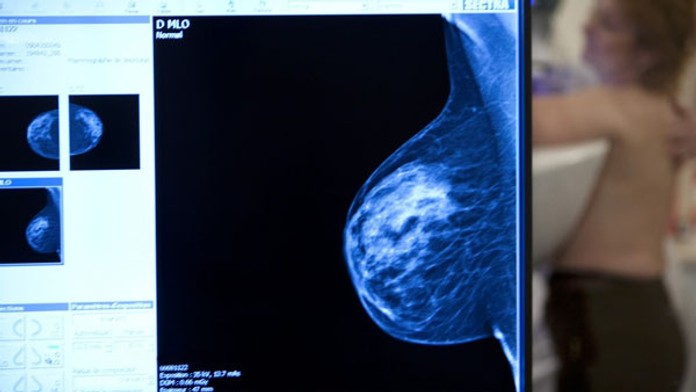

Štúdia spochybnila význam mamografického vyšetrenia prsníka

Rozsiahla kanadská štúdia spochybnila význam preventívneho vyšetrovanie mliečnej žľazy u žien. Mamografické vyšetrenie síce zachytí nádor včas, avšak podľa štúdie je úmrtnosť na rakovinu prsníka u žien, ktoré screening prekonali, rovnaká ako u tých, ktoré ho nemali. Výskum trval zhruba 25 rokov a zapojilo sa do neho 90 -tisíc žien.

Štúdia, ktorú minulý týždeň zverejnil časopis The British Medical Journal, náhodným spôsobom vyberala Kanaďanky, ktoré potom pravidelne podstupovali mamografické vyšetrenie, vyšetrenie prsníka v ordinácii, alebo si ich vykonávali samy.

Výskumníci chceli zistiť, či je výhoda v tom, keď sa rakovina prsníka zistí vo fáze, kedy je nádor tak malý, že sa nedá ani nahmatať. Došli ale k zápornej odpovedi.

O prínosoch mamografického skríningu sa debatuje už dlho. Žiadna krajina okrem Švajčiarska ale zatiaľ nenaznačila, že skríning zastaví.